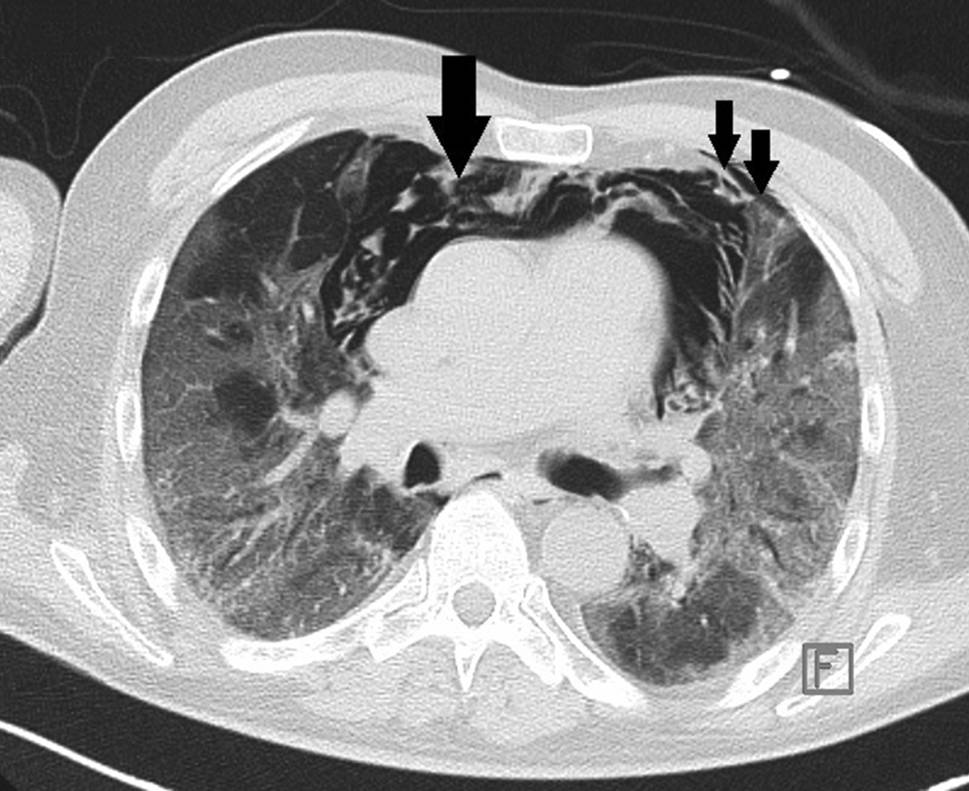

Ein 75-jähriger Patient wurde wegen Thoraxschmerz und Dyspnoe in präkollaptischem Zustandsbild vorgestellt. Vor einigen Tagen habe Husten bestanden, der aber wieder abgeklungen sei. Die PCR auf SARS-CoV‑2 war positiv. Anamnestisch lag arterieller Hypertonus vor. Ein akutes Koronarsyndrom wurde mittels EKG, Echokardiographie und Enzymdiagnostik ausgeschlossen, die Kreislaufparameter waren unauffällig, der Patient afebril. Unter 2 l O2/min über Nasenbrille lag die Sauerstoffsättigung bei 94 %. Im Labor bestanden Leukozytose (20,4 G/l), Erhöhung von Ferritin auf 752 ng/ml (NW 18–360) und von IL‑6 auf 29,2 pg/ml (NW 0–7). Das Thorax-CT zum Aufnahmezeitpunkt zeigte SARS-CoV-2-typische Infiltrate sowie einen Pneumothorax links (Abb. 5). Nach Anlage einer Thoraxdrainage links besserte sich die respiratorische Situation rasch. Unter kontinuierlicher O2-Gabe (4 l/min) über Nasenbrille erfolgte der Transfer an die Normalstation. Nach Einleitung leitlinienkonformer Therapie mit Antibiotika und Kortikosteroiden waren die Entzündungswerte regredient. Infolge persistenter, pulmopleuraler Fistel reexpandierte die linke Lunge jedoch trotz Anlage eines weiteren Drains nicht. Das Thorax-CT ergab Zeichen inhomogener Lungendestruktion mit bilateralen Fibrosearealen und Pneumatozelen (Abb. 6). Infolge ausgeprägter Kollateralventilation war das auf ein Subsegment fokussierte Setzen eines Ventils nicht möglich. Das Positionieren von mehreren Ventilen schied aus funktionellen Gründen aus.

Abb. 5

Pneumothorax (Pfeil) ohne Weichteilemphysem

Abb. 6

Pneumothorax (Pfeil) trotz einliegender Thoraxdrainage (Stern), Pneumatozele (2 Pfeile)

Eine thorakoskopische Intervention schied ebenfalls aus, da aus anästhesiologisch-beatmungstechnischer Sicht weder die seitengetrennte Ventilation mit Kollabieren der zu operierenden Lunge noch das Setzen eines Pneumothorax möglich waren. Bei der Thorakotomie am Tag 10 fand sich eine ausgeprägte bronchopleurale Fistel, ausgehend von einer rupturierten Pneumatozele.

Das Areal wurde keilreseziert. Nach problemlosem postoperativem Verlauf wurde der Patient am Tag 16 ohne respiratorische Unterstützung nach Hause entlassen.